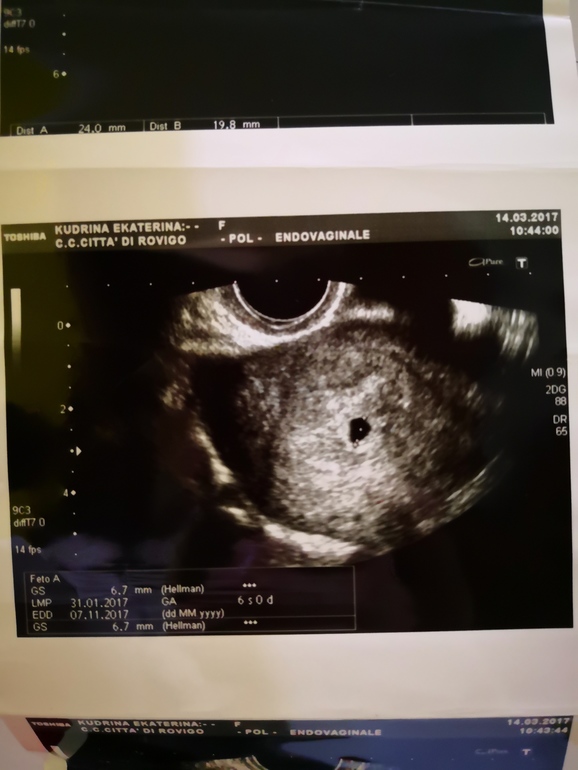

Вот, Оля, это 6 неделя и Алису ещё не видят. 🤷♀️